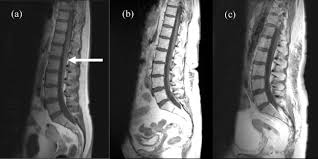

Cauda Equine Syndrome As The Primary Symptom Of Leptomeningeal Metasta Ott

Scielo Brasil Mortality Is Higher In Patients With Leptomeningeal Metastasis In Spinal Cord Tumors Mortality Is Higher In Patients With Leptomeningeal Metastasis In Spinal Cord Tumors